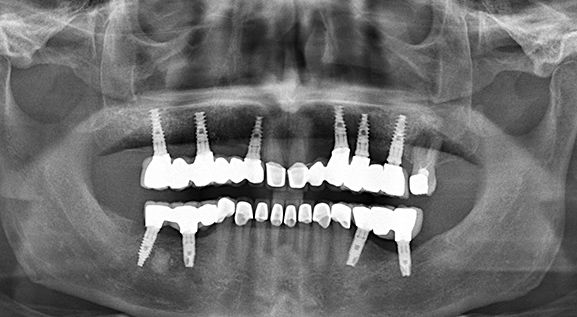

Panoramic xray - Cebu

The Panoramic x-ray, is a two-dimensional (2-D) dental x-ray examination that captures all completely the mouth in a single image this are the following the teeth, upper and lower jaws, surrounding structures and tissues.

6 Reasons why use X-ray panoramic for your dental implants here in Cebu Philippines